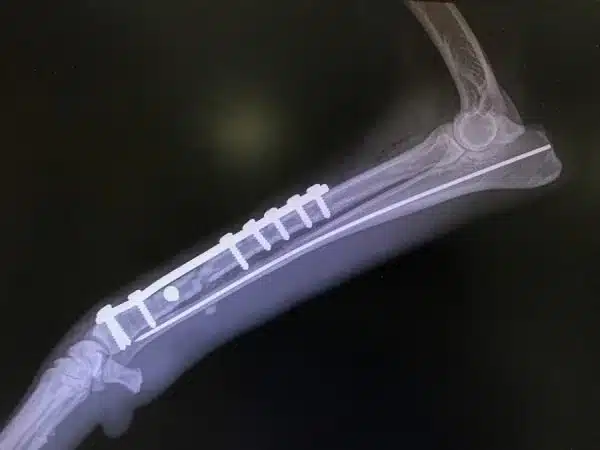

Pins and Wires

Another way to treat the fractures is with pins and wires. These pins are used to stabilize the broken bone from the inside. It stabilizes the bone from the inside and helps in the proper healing.

Broken bone pieces are held together with the help of a metal pin. This metal pin is inserted in the center of the bone to support the full bone. Wires are also used to provide extra care.

- It is mainly used for pets who have major injuries and have long bone fractures.

- It is used for fractures that cannot be treated or stabilized from the outside of the bone.

- It is used for severe injuries in pets.

- Strong support for the bone is there from inside.

- Pins and wires align the bones perfectly during the healing process.

- This surgery is performed with anesthesia.

- A procedure is also needed to remove all the pins after the healing is completed.

- Infection can also occur if the healing is not done properly.